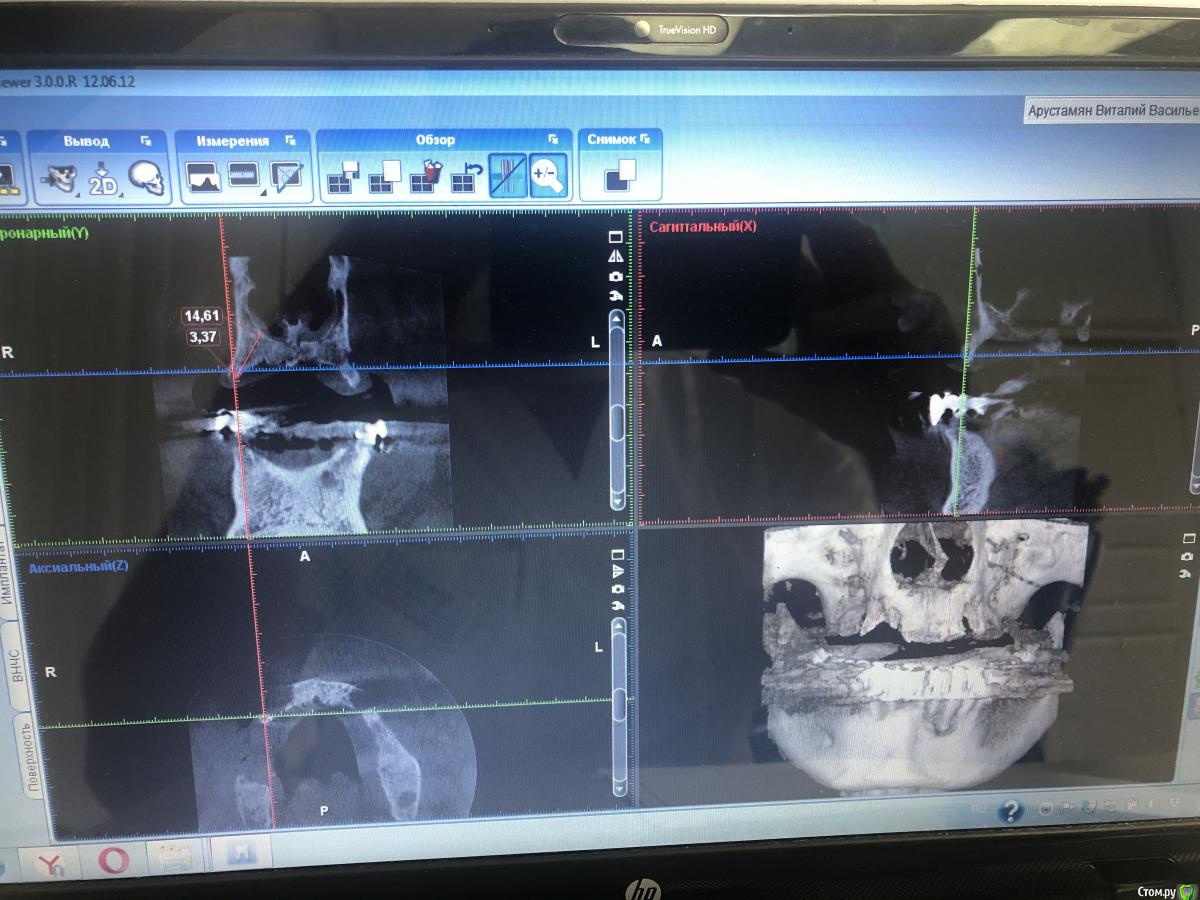

Александр07 Опубликовано 1 июля, 2020 Поделиться Опубликовано 1 июля, 2020 Коллеги доброго дня, пац 55-60 лет, хочет чтобы было красиво и крепко держалось, такая ситуация во рту, планируем операцию на вчКак видите примерно в обл 1.4-1.6 дефект по высоте, размышляю по поводу установки 1.1,1.3, 2.2,2.4 с расщеплением в обл 1.3, под протез на балке, Врем конструкция на импл , даже при условии что получится без большой подсадки, не рискнул бы- крупный мужчина, будет давать нагрузку, если ставить Мини импл то планировал бы позиции 2.1,2.5, 1 сегмент пока не ясно куда ставить ) По аугментации в обл 1.5-1.6, что посоветуете- делать /не делать, одновременно с фронтом или отдельно, или ограничиться тем планом по балке что написал выше , В обл 2.5-2.6 синус нужен trim.F286E467-8CC6-421B-ACE6-47434003E04E.MOV Ссылка на комментарий

Bier Опубликовано 1 июля, 2020 Поделиться Опубликовано 1 июля, 2020 мне не нравится вариант с расщеплением.тут нужно еще КТ покрутить 1 Ссылка на комментарий